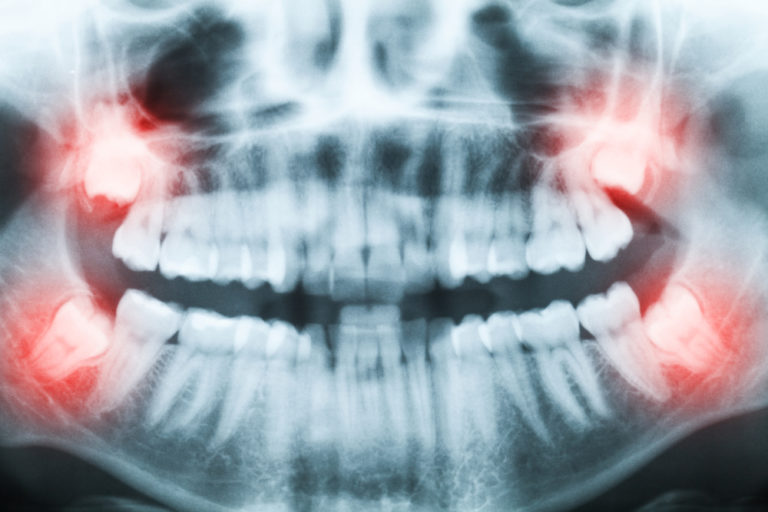

A panoramic x-ray is a 2D x-ray that produces a flat image of the entire mouth. This includes the teeth, upper and lower jaws, and tissues, all in one film. A panoramic x-ray or panorex helps your dentist assess, diagnose, and treat issues related to your mouth. They’re beneficial in planning treatments, such as extractions, dentures, and implants. Unlike intraoral scanners, a panorex is taken outside of the mouth. Your dentist or the technician asks you to bite down on a material to ensure proper teeth alignment. The machine then rotates outside your head, from one side of the jaw to the other, while you stay still.